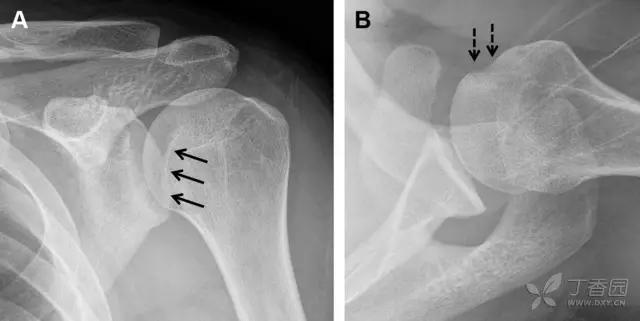

23 单纯肱骨大结节骨折

与其它肱骨近端骨折不同,单纯肱骨大结节骨折常发生于年轻人。肱骨大结节骨折常由撞击或剪切/撕脱损伤所致:

撞击包括直接撞击、肩峰撞击、上关节盂撞击(极度外展时);

剪切/撕脱损伤常发生于肩关节前脱位。

在常规前后位片上,大结节与肱骨头重叠,骨折不易发现,外旋位前后位片有助于诊断。

图 1 大结节骨折。(A)脂肪抑制序列斜冠状位 MRI,显示肱骨大结节线性骨折无移位(箭头)与周围骨水肿;(B)外旋位前后位(AP)片,证实大结节骨折(箭头),典型的骨折愈合过程中的骨吸收表现;(C、D)初诊时内旋位、外旋位前后位片,初诊时漏诊,仔细回顾影像,内旋伞下可见双密度影(椭圆),骨皮质中断(箭头)